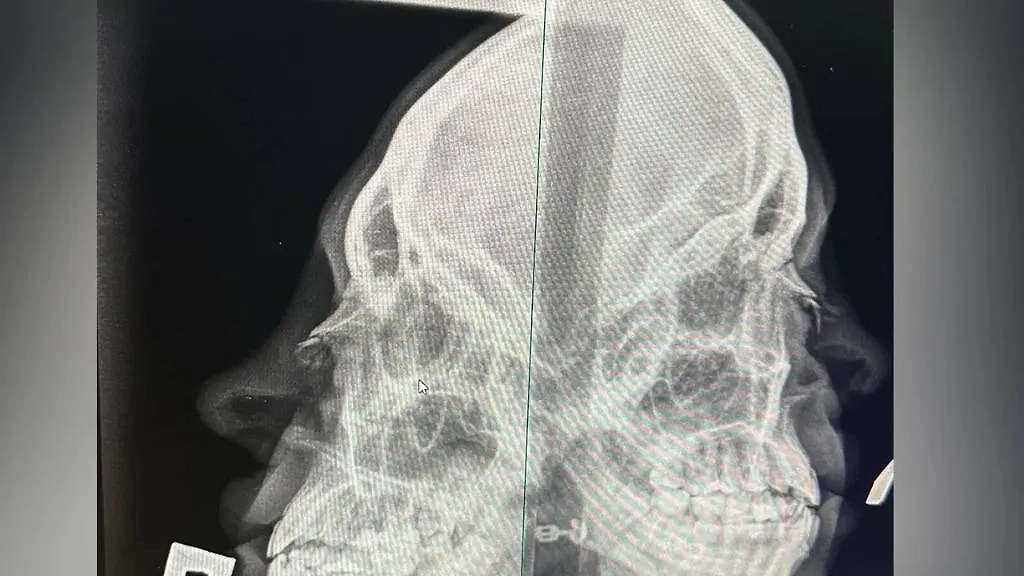

Как оказалось, мужчина с одного удара сломал хрупкой девушке нос: в больнице ей сообщили, что требуется операция. Пострадавшая написала заявление в полицию. Неадекватного бойца сейчас разыскивают.